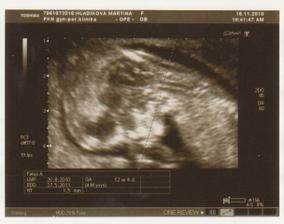

NT screening 12+4tt

Marti, nádherný fotečky, to je bojovník, vybojoval si život a tak to dobře dopadne a třeba budeš celou dobu zavřená. Dějou se i zázraky. A to je dobře.